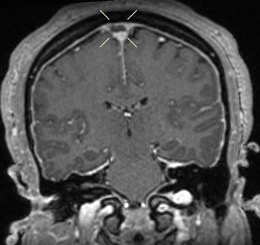

Diagnostic Testing. The patient’s CT brain imaging revealed a small amount of air in both frontal horns of the lateral ventricles (Figure 1). Her brain CTA revealed distension of the superior sagittal sinus (SSS), inferior sagittal sinus, transverse sinus, and vein of Galen and an extra-axial SSS defect (Figures 2-4). The initial report of the MRI brain with and without contrast redemonstrated trace pneumocephalus but was otherwise unremarkable. Later review after 10 days, revealed pachymeningeal enhancement, venous sinus distension, and a filling defect in the SSS suggestive of venous sinus thrombosis (Figures 5, 6). Her MRI of the cervical spine did not reveal another cause of neck pain, and her urine protein was negative.

Fig. 5. Postcontrast coronal T1 images confirm the superior sagittal sinus filling defect seen on CT.